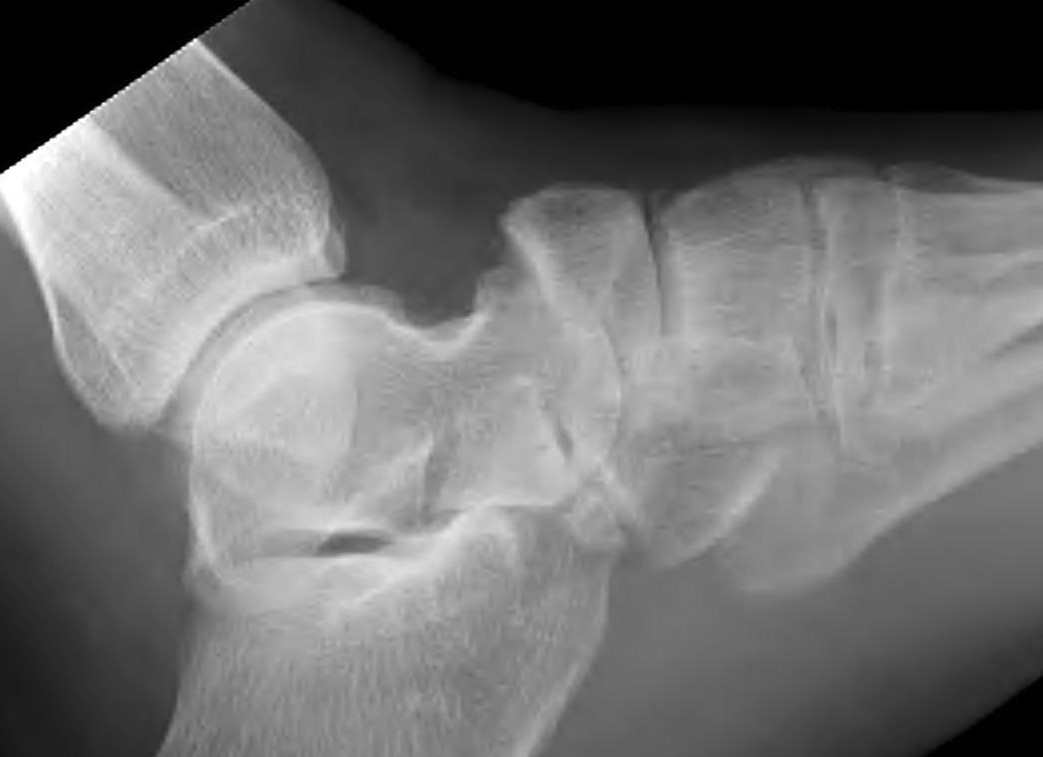

Xray

Displaced navicular stress fracture